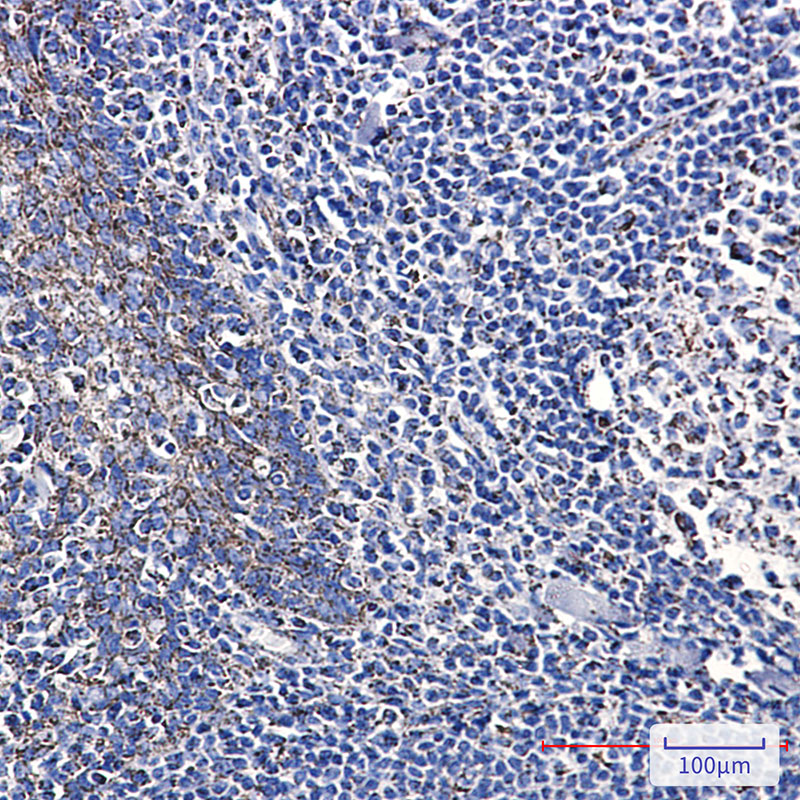

IHC 1/50-1/100 Human,Mouse,Rat

Citrate synthase (CS) is a key enzyme in the tricarboxylic acid (TCA) cycle, catalyzing the condensation of acetyl-CoA and oxaloacetate to form citrate. As a mitochondrial matrix protein, it serves as a metabolic hub linking carbohydrate, lipid, and amino acid metabolism. Antibodies targeting citrate synthase are widely used as experimental tools to study mitochondrial function, cellular energy metabolism, and metabolic adaptations in diseases such as cancer, neurodegeneration, or metabolic disorders.

These antibodies are typically developed in hosts like rabbits or mice using purified recombinant CS protein or peptide immunogens. Both monoclonal and polyclonal variants are available, with applications including Western blotting, immunofluorescence, immunohistochemistry, and ELISA. Specificity is critical, as CS is highly conserved across eukaryotes, and cross-reactivity with bacterial CS isoforms must be ruled out in certain models.